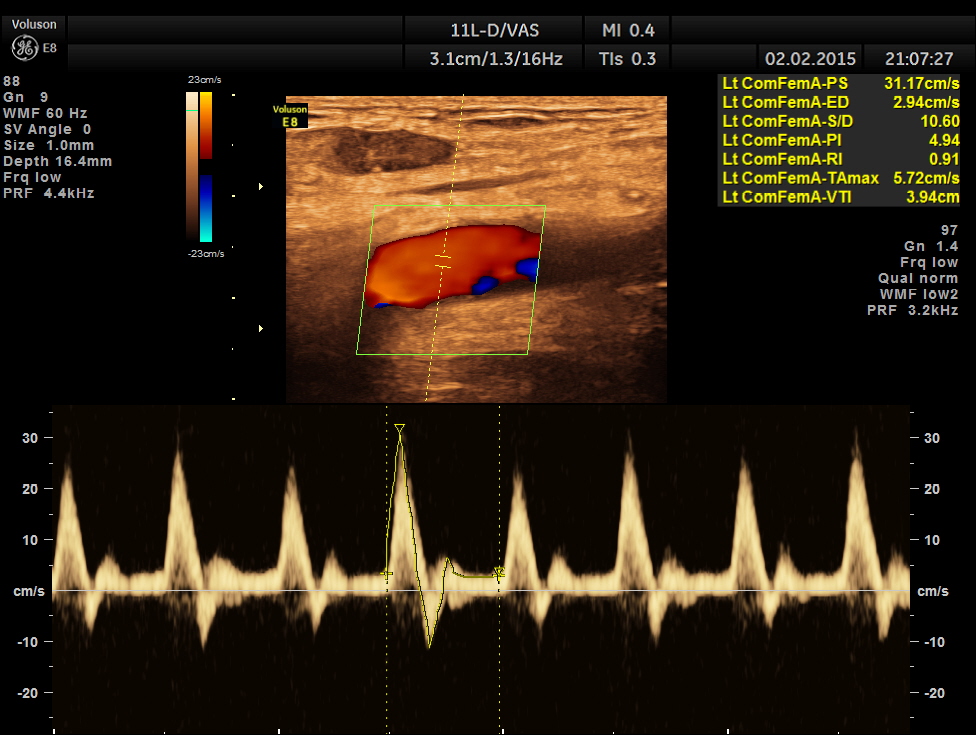

the left common femoral artery showed normal flow